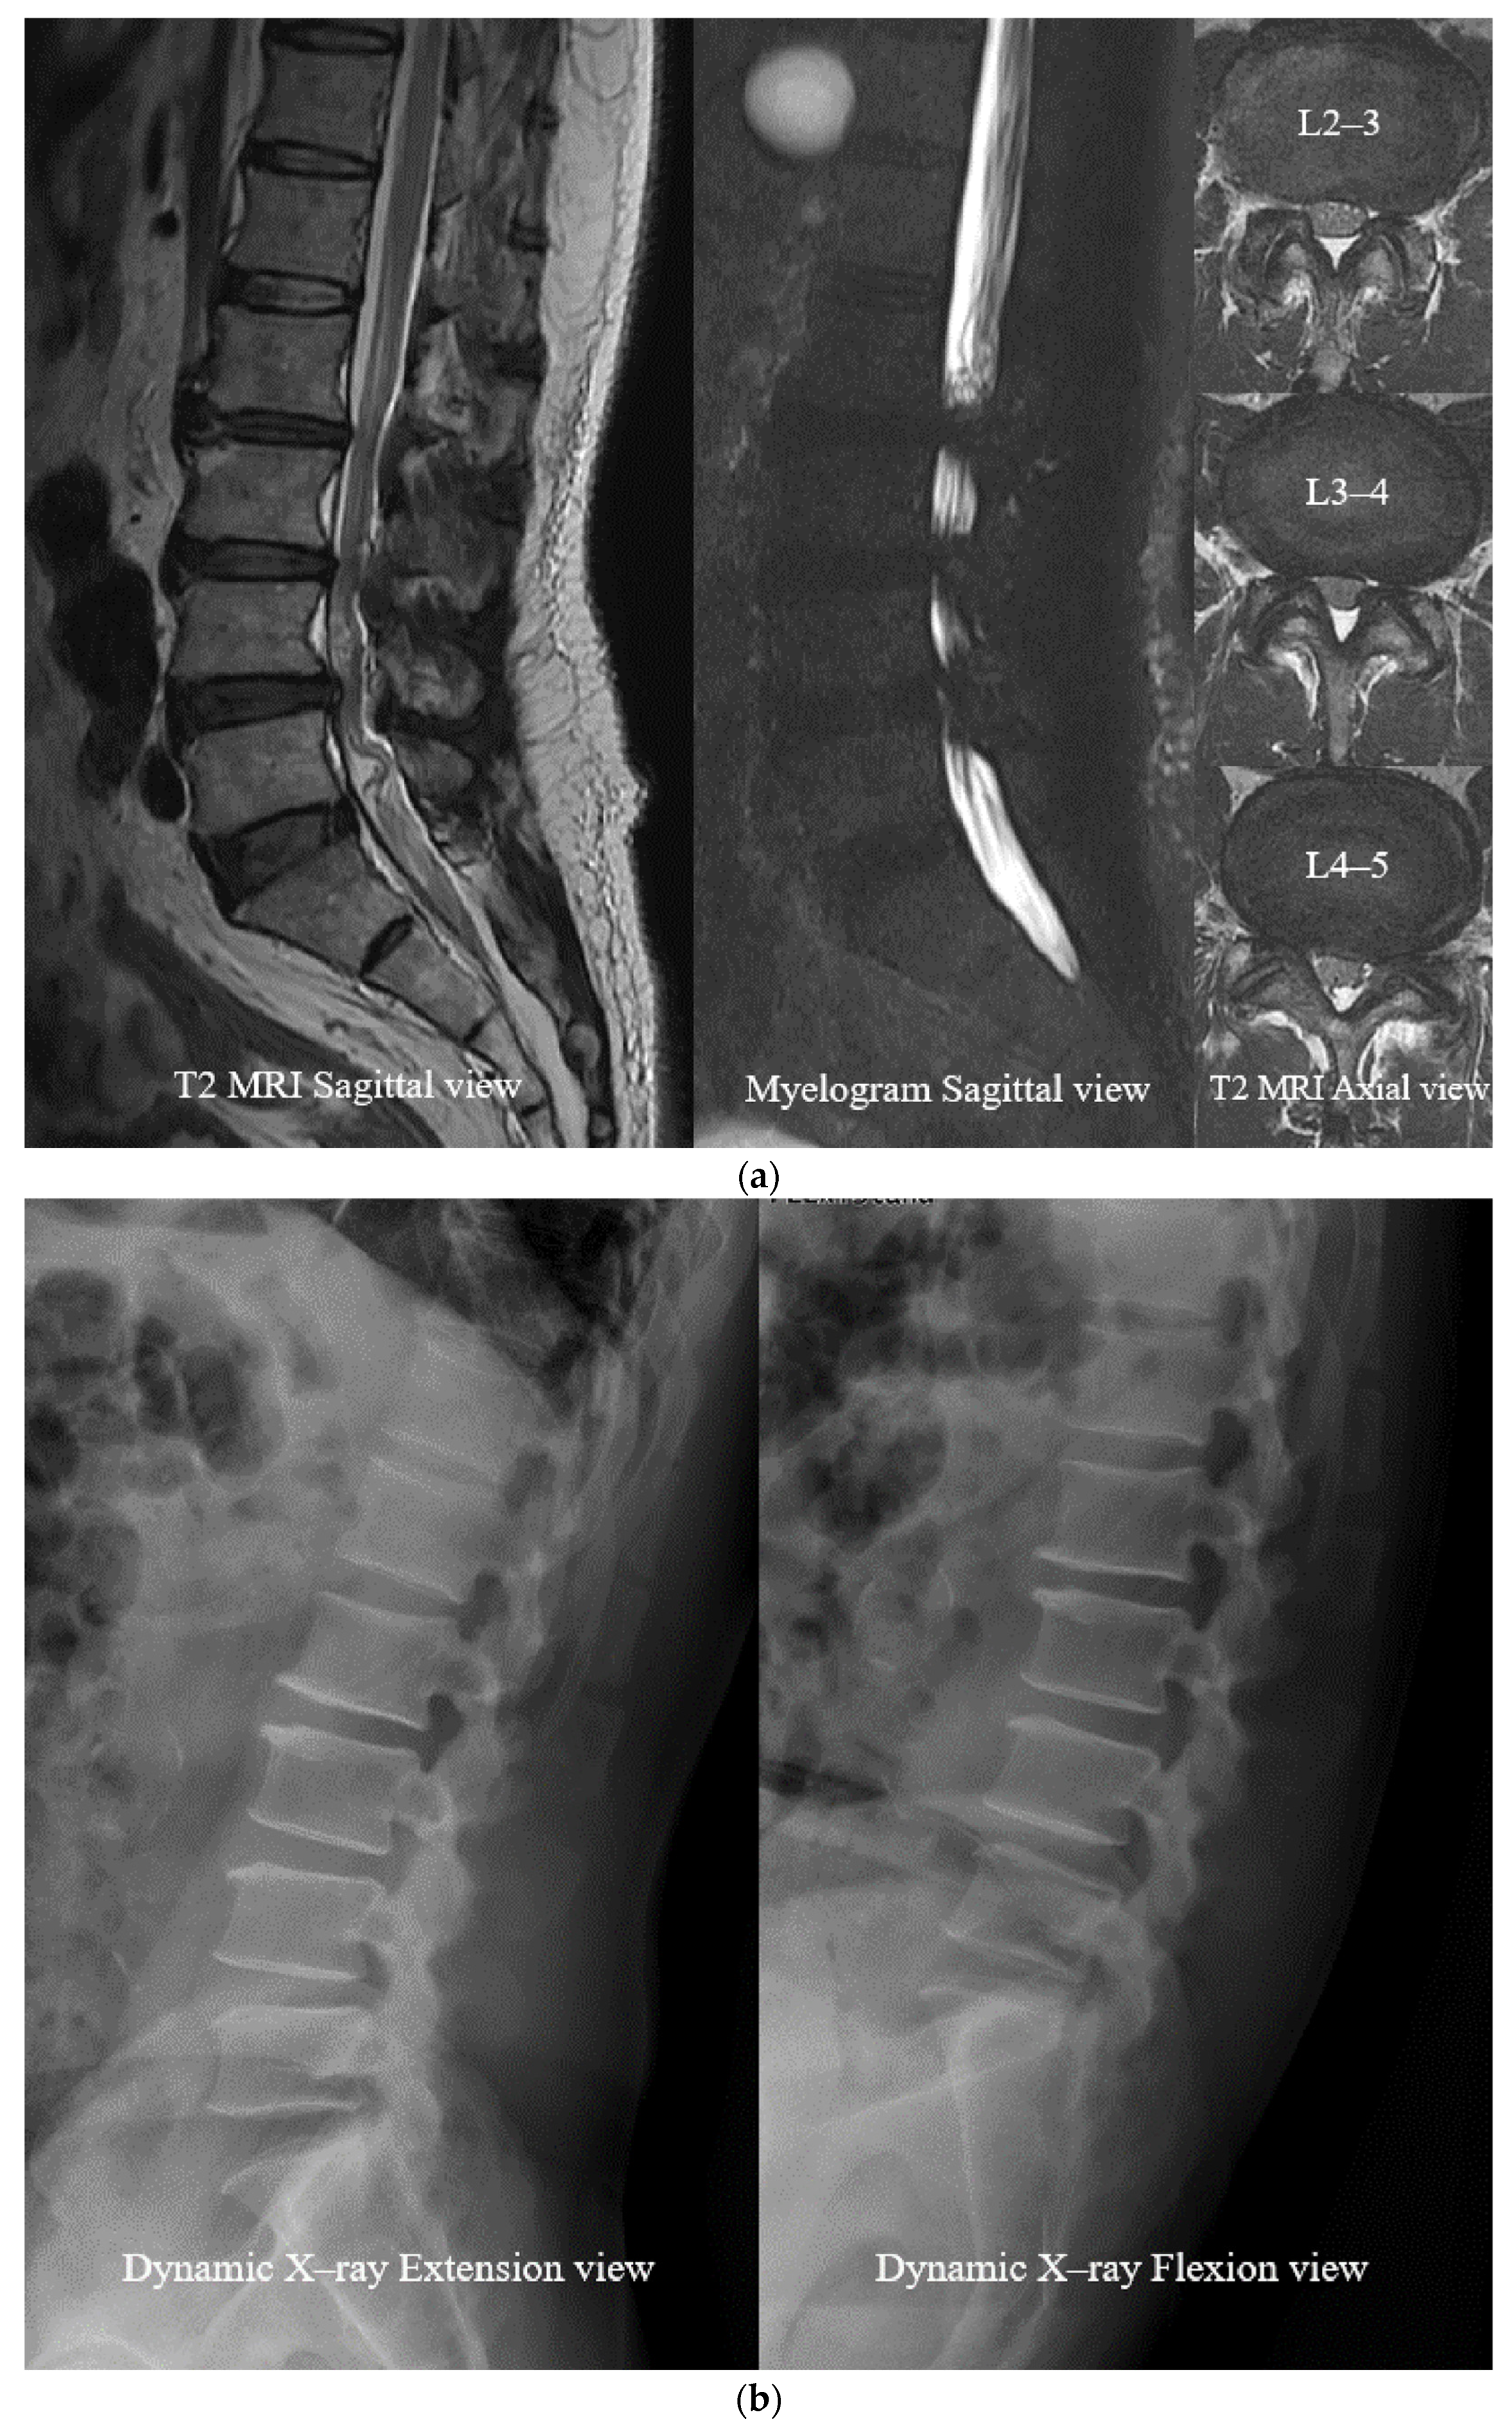

- Open Midline Decompression

- Ligament Reconstruction